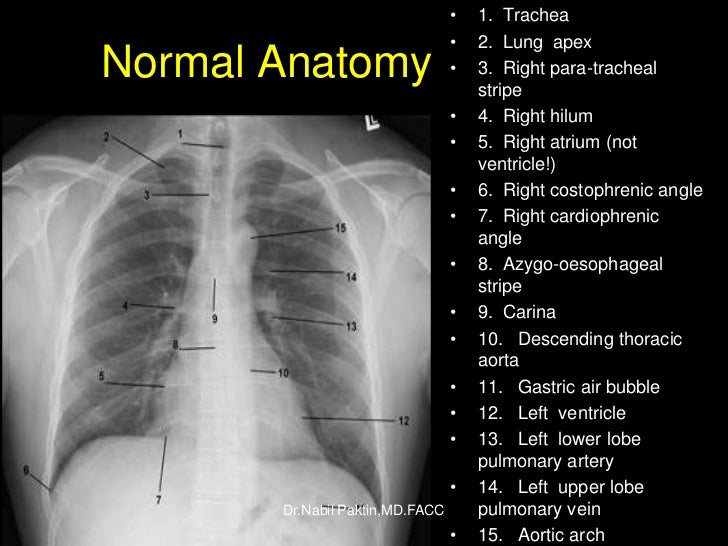

Normal Chest Xray Labeled Chest X-Ray Interpretation Explained Clearly - How To Read A Cxr In fact every radiologst should be an expert in chest film reading. Understand the key concepts of reading a chest radiograph with this medical. 20 may, 2024by zach north. A free medical lecture on chest x ray (cxr) interpretation. Chest radiographs are used to aid the diagnosis, treatment and management of a range of cardiovascular and. The interpretation of a. Chest X-Ray Interpretation Explained Clearly - How To Read A Cxr.